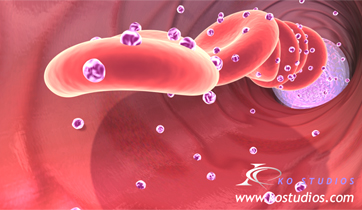

EnCompass F2 Device for cerebral embolic protection system in TAVR procedures

EnCompass Technologies

EnCompass’ F2 filter has pores small enough to block most emboli to the brain while preserving blood flow. During the TAVR procedure, 360-degree wall apposition of the filter in the aortic arch prevents migration. The filter, attached to a self-expanding, nitinol stent, is easy to insert, deploy and retrieve, according to the company. Copyright ©2021 KO Studios.